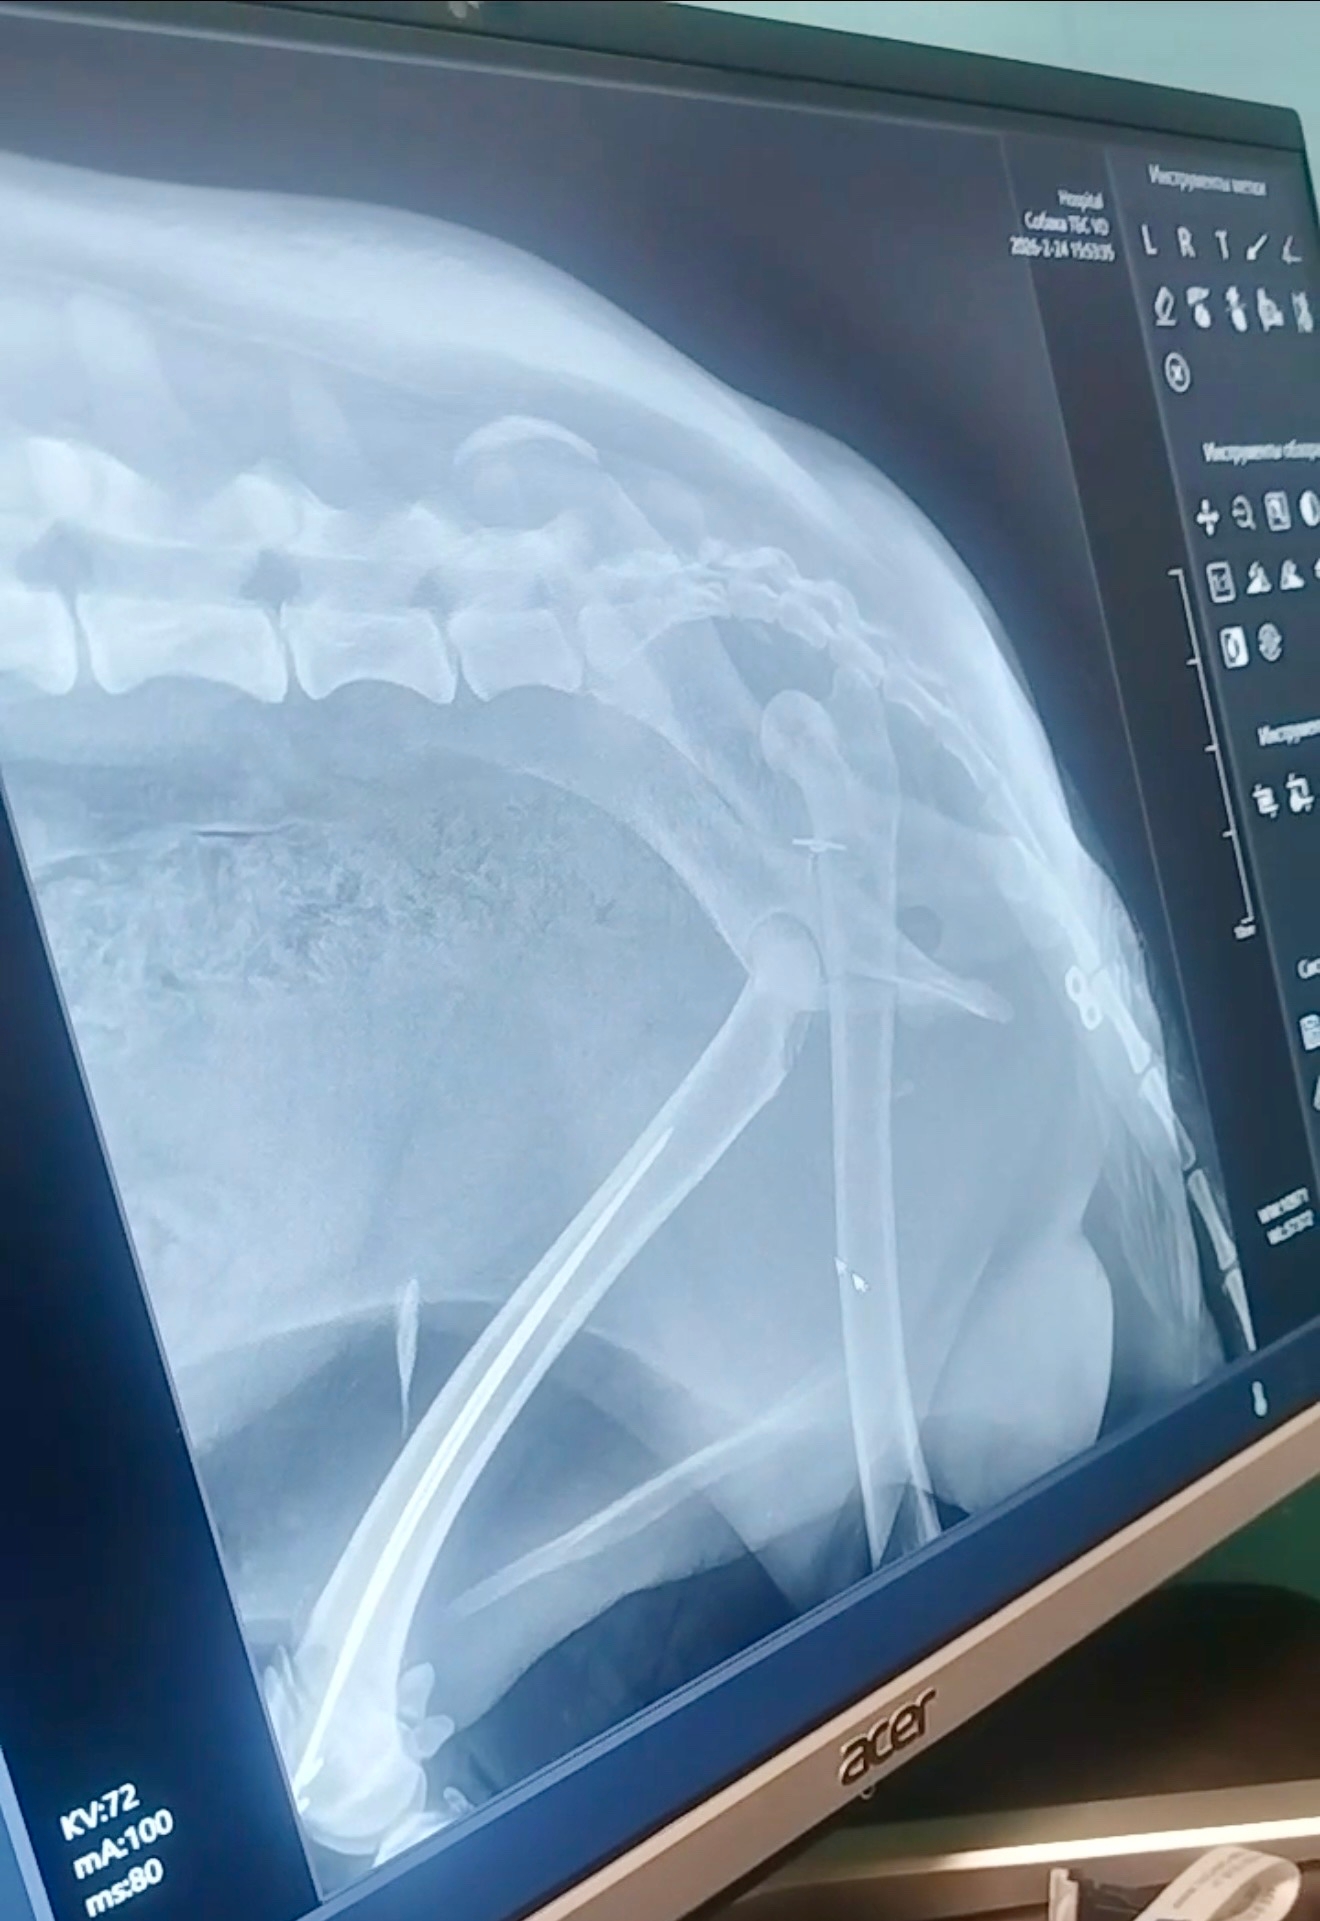

В первой клинике провели некачественную операцию, необходимо снимать воспаление и переделывать операцию 😭😭😭

Прошу всех неравнодушных помочь нам, иначе собака погибнет: у него сломан таз и коленная чашечка.